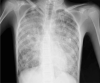

Case presentation: A-15 year-old Saudi male presented to the emergency department with a history of shortness of breath and low oxygen saturation. High-resolution computed tomography of his chest showed a global crazy-paving pattern. Autoantibodies against granulocyte-macrophage colony-stimulating factor were detected in his serum. A diagnosis of the autoimmune form of pulmonary alveolar proteinosis was confirmed after excluding other possible causes. The patient improved after he underwent whole lung lavage under general anesthesia, and he was independent of oxygen therapy after 6 months of follow-up.